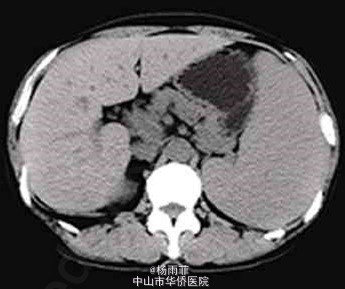

体格检查:体温37℃,脉搏84次/分,血压138/89mmHg,神志清楚,皮肤黏膜无苍白及黄染,浅表淋巴结未触及,颈软,双肺呼吸音清晰,心律齐,未闻及杂音,腹膨隆,触诊质软,无压痛,肝脾肋下未触及,移动性浊音阳性,双下肢不肿。 血常规检查:白细胞3.32×109/L,红细胞3.19×1012/L,血红蛋白93g/L,血小板273×109/L,尿常规及大便常规检查正常,肝肾功能正常,血清白蛋白正常,血淀粉酶534U/L(正常值125U/L),血清肿瘤标志物(甲胎蛋白、癌坯抗原、糖链抗原19-9)正常。 腹水常规检查:李凡他试验阴性,红色,细胞总数54473×106/L,白细胞473×106/L,单个核细胞95%,腹水生化检查:总蛋白35.9g/L,总胆固醇1.46mmol/L,乳酸脱氢酶122U/L,腺苷脱氨酶9U/L。腹水淀粉酶340U/L,腹水-血清白蛋白梯度14g/L。腹水细胞学检查见部分红细胞、淋巴细胞及间皮细胞,未见癌细胞。 乙型肝炎病毒表面抗原阴性,丙型肝炎病毒抗体阴性。 影像学检查: 胃镜检查示胃底静脉曲张,食管与胃黏膜未见异常; 门静脉CT成像显示脾静脉全程、肠系膜上静脉与脾静脉汇合处管腔明显变窄,以脾静脉为著,胃底静脉曲张,门静脉主干及肝内分支形态、走行未见明显异常,胰体头部钙化灶,尾部形态饱满,边缘模糊,见数个囊状影;腹腔大量积液。